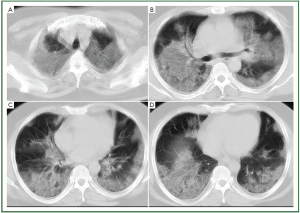

According to our inclusion criteria, all the patients had CT evidence of lung abnormalities consistent with influenza H1N1 pneumonia. The lung lesions were of typical virus infection, including ground-glass opacity (hazy areas of increased attenuation without obscuration of the underlying vessels), consolidation (homogeneous opacification of the parenchyma with obscuration of the underlying vessels), reticular opacities, linear opacities, interlobular septal thickening, and mixed pattern (Figures 1,2).

Figure 1. 28-year-old woman with H1N1 viral pneumonia. No history of chronic pulmonary disease. Chest CT was obtained day 6 after onset of influenza symptoms. CT images (A-B) demonstrate ground-glass opacities and consolidation predominantly in the middle zone and lower zone of the left lung, and minor patchy ground-glass opacities in the lower zone of the right lung. There is bilateral mild pleural involvement. The lung lesion score is 8.

Figure 2. 44-year-old man with H1N1 viral pneumonia in critical condition. No history of chronic pulmonary disease. Chest CT was obtained 6 days after the onset of the influenza symptoms. Bilateral and widespread ground-glass opacities in all six lung zones are demonstrated (A-D). There is bilateral mild pleural effusion. The chest lesion score is 19.